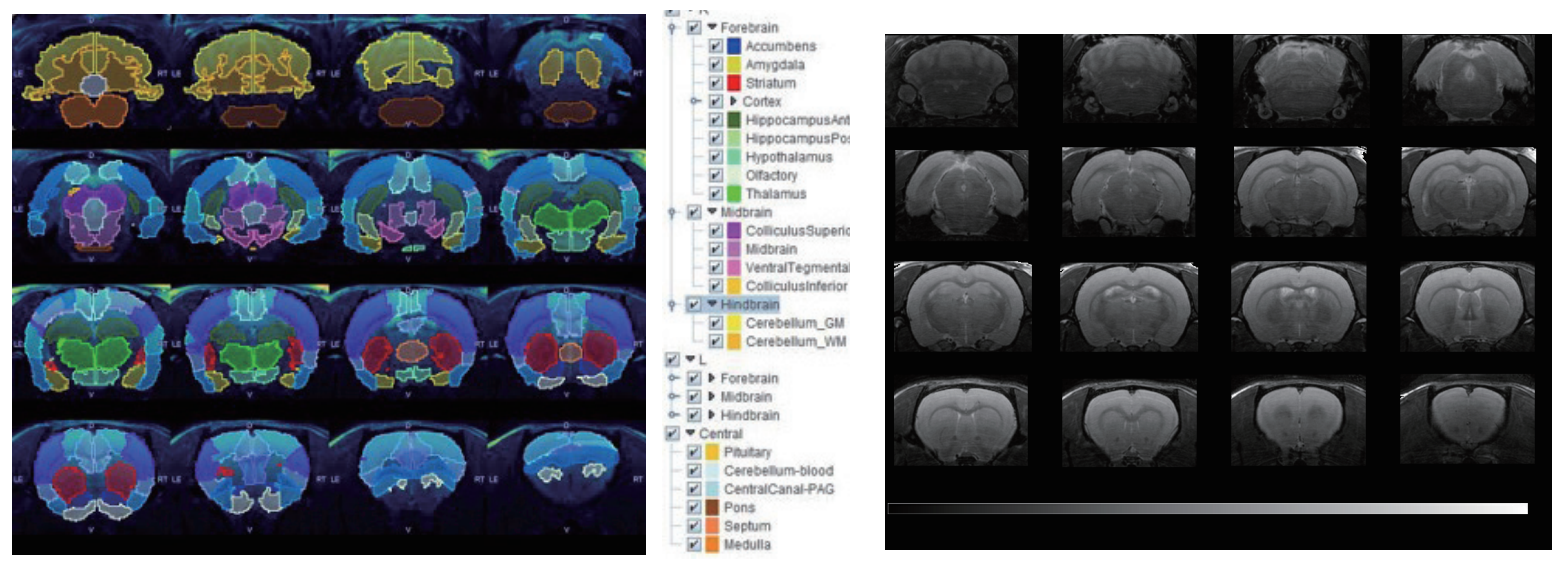

7T磁共振下大鼠腦部RARE影像,使用PMOD軟件分割。